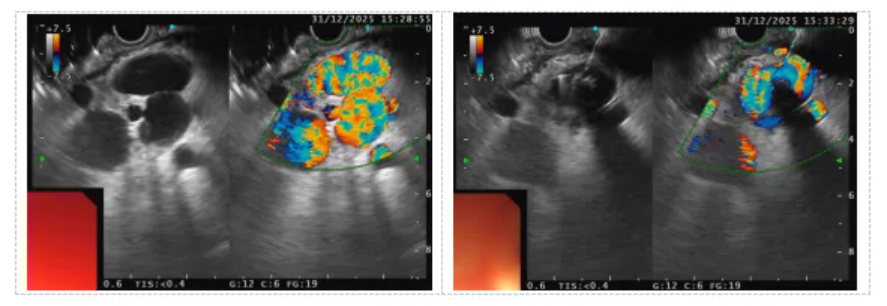

在ICU保驾护航下,手术于气管插管全麻中有序开展。团队首先借助纵轴超声内镜,如同配备“高清透视眼”与“血流导航仪”,精准锁定目标血管的位置、形态及血流信息。

在超声实时引导下,张宁主任经微细穿刺针将两枚微型弹簧圈准确送达目标血管,随后注入适量组织胶。弹簧圈迅速形成“钢筋骨架”,与凝固的组织胶(“混凝土”)紧密结合,在曲张静脉及异常分流道内构建起稳固的“钢筋混凝土”式栓子。超声屏幕上可见原活跃血流信号立即消失,表明出血源头被成功封堵。随后,团队对食管及其他胃底曲张静脉进行了套扎和加固治疗,一次性完成了多部位复杂静脉曲张的联合处理。